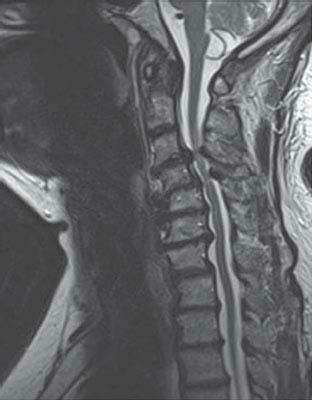

1. A 50-year-old man presents with gradually progressive weakness in his upper extremities over the past 6 months. A cervical MRI is obtained, which is shown in Figure 11.4. On the basis of the location of the lesion, on examination you will find:

Horner’s syndrome is seen in patients with spinal cord lesions above T1, where the spinal sympathetic tract synapses before exiting the spinal cord (discussed in Chapters 1 and 10). This patient has a lesion above T1, and will likely have a Horner’s syndrome.

As shown in Figure 11.4, this patient has an intramedullary lesion producing signal abnormality in the cervical cord from C1 to C6. Because the lesion has developed gradually, the patient will likely have myelopathic findings with upper motor neuron manifestations below the lesion. Therefore, the patient will likely have increased tone with spasticity and hyperreflexia below the level of the lesion. Some cases will demonstrate lower motor neuron findings at the same level of the lesion due to involvement of anterior horn cells, in this case probably in the upper extremities. A sensory level is helpful for clinical localization of the level of the lesion. The level of the nipple line correlates with T4. Other levels that are useful landmarks are the base of the neck (C4), umbilicus (T10), groin (L1), and anal region (S5). In this case the lesion is in the cervical region; therefore, the patient’s sensory level is likely above the nipple line. The presence of superficial abdominal reflexes is a normal finding, and their absence indicates a corticospinal tract lesion above the T6 segment.